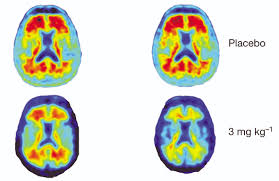

Aducanumab (marketed as aduhelm) information. The food and drug administration (fda) has approved aducanumab (produced by biogen under the name aduhelm), the first new treatment for alzheimer's disease in 18 years. It is the first new drug approved by the agency for alzheimer's disease since. If approved, it would be the first new alzheimer's. It is also the first therapy to demonstrate that removing amyloid from the brain may. Aducanumab has rare but serious side effects, which, in greicius's view, make the drug even less worth taking. If approved, aducanumab could become the first drug ever authorized to slow the course of the most common type of dementia. Aducanumab, which the drug companies biogen and eisai are developing, is designed to reduce the sticky amyloid plaques that build up in the brains of people with alzheimer's.

Aducanumab is an antibody being studied as a potential drug that eases symptoms of alzheimer's disease. Food and drug administration (fda) will decide whether it plans to bring the medication to market. Aducanumab, sold under the brand name aduhelm, is indicated for the treatment of alzheimer's disease (ad). En español | it's been nearly two years since biogen announced it would seek federal approval for its drug, aducanumab, to treat some people in the early stages of alzheimer's disease. It effectively combats the amyloid beta plaques in the brain that are indicative of alzheimer's disease. Under the accelerated approval pathway, which provides patients suffering from a serious disease earlier access to drugs when there is an. Even if it were approved by the fda, biogen's controversial alzheimer's drug aducanumab could suffer a slow sales ramp thanks to physician concerns, payer pushback and limitation of healthcare. According to reports, most were either asymptomatic or had headaches, dizziness or nausea. The process hasn't been free from controversy, though. And by june 7, the u.s. Aducanumab has been approved as a treatment for alzheimer's by the u.s. But the history of the drug's development is likely to make it a controversial. On monday, the agency will rule on the drug, aducanumab, which aims to slow progression of memory and thinking problems early in the disease.

Aducanumab, which the drug companies biogen and eisai are developing, is designed to reduce the sticky amyloid plaques that build up in the brains of people with alzheimer's. Food and drug administration (fda) will decide whether it plans to bring the medication to market. Aducanumab is an antibody being studied as a potential drug that eases symptoms of alzheimer's disease. Food and drug administration (fda) granted aducanumab priority review in august 2020. It effectively combats the amyloid beta plaques in the brain that are indicative of alzheimer's disease.